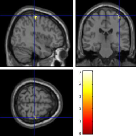

Once the reduced FOV images are available, the proposed pMRI 4D-UWR-SENSE algorithm and its early UWR-SENSE version have been utilized in a final step to reconstruct the full FOV EPI images and compared to the mSENSE Siemens solution. For the wavelet-based regularization, dyadic Symmlet orthonormal wavelet bases [48] associated with filters of length 8 have been used over resolution levels. The reconstructed EPI images then enter in our fMRI study in order to measure the impact of the reconstruction method choice on brain activity detection. Note also that the proposed reconstruction algorithm requires the estimation of the coil sensitivity maps (matrix in Eq. (2)). As proposed in [4], the latter were estimated by dividing the coil-specific images by the module of the Sum Of Squares (SOS) images, which are computed from the specific acquisition of the -space centre (24 lines) before the scans. The same sensitivity map estimation is then used for all the compared methods. Fig. 5 compares the two pMRI reconstruction algorithms to illustrate on axial, coronal and sagittal EPI slices how the mSENSE reconstruction artifacts have been removed using the 4D-UWR-SENSE approach. Reconstructed mSENSE images actually present large artifacts located both at the centre and boundaries of the brain in sensory and cognitive regions (temporal lobes, frontal and motor cortices, …). This results in SNR loss and thus may have a dramatic impact for activation detection in these brain regions. Note that these conclusions are reproducible across subjects although the artifacts may appear on different slices (see red circles in Fig. 5). One can also notice that some residual artifacts still exist in the reconstructed images with our pipeline especially for . Such strong artifacts are only attenuated and not fully removed because of the high level of information loss at .

| mSENSE | 4D-UWR-SENSE | ||